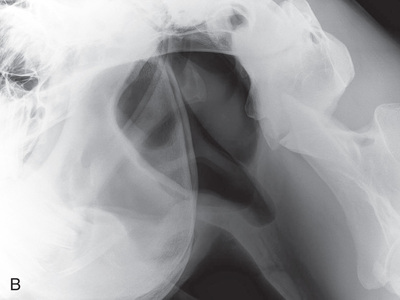

General anesthesia is required for the pelvic radiographic study of a large animal patient. Young foals (or calves) can be successfully radiographed in the field, whereas larger patients (horses or cows) must be radiographed in the hospital setting because of the specific high-powered radiographic equipment required, such as a mobile or ceiling-mounted unit, to provide proper output (high kV exposure). Views may be segmented to obtain a complete pelvic view (multiple images used for a single view). If using film, the use of a table with an embedded cassette tunnel is preferred to increase ease of positioning and cassette exchange. Due to the thickness of this region, the use of a grid is suggested.

Before administration of a general anesthetic, special consideration must be given to the anesthesia recovery process for patients with pelvic fractures or luxation. As a result, a pelvic radiographic study may be contraindicated.